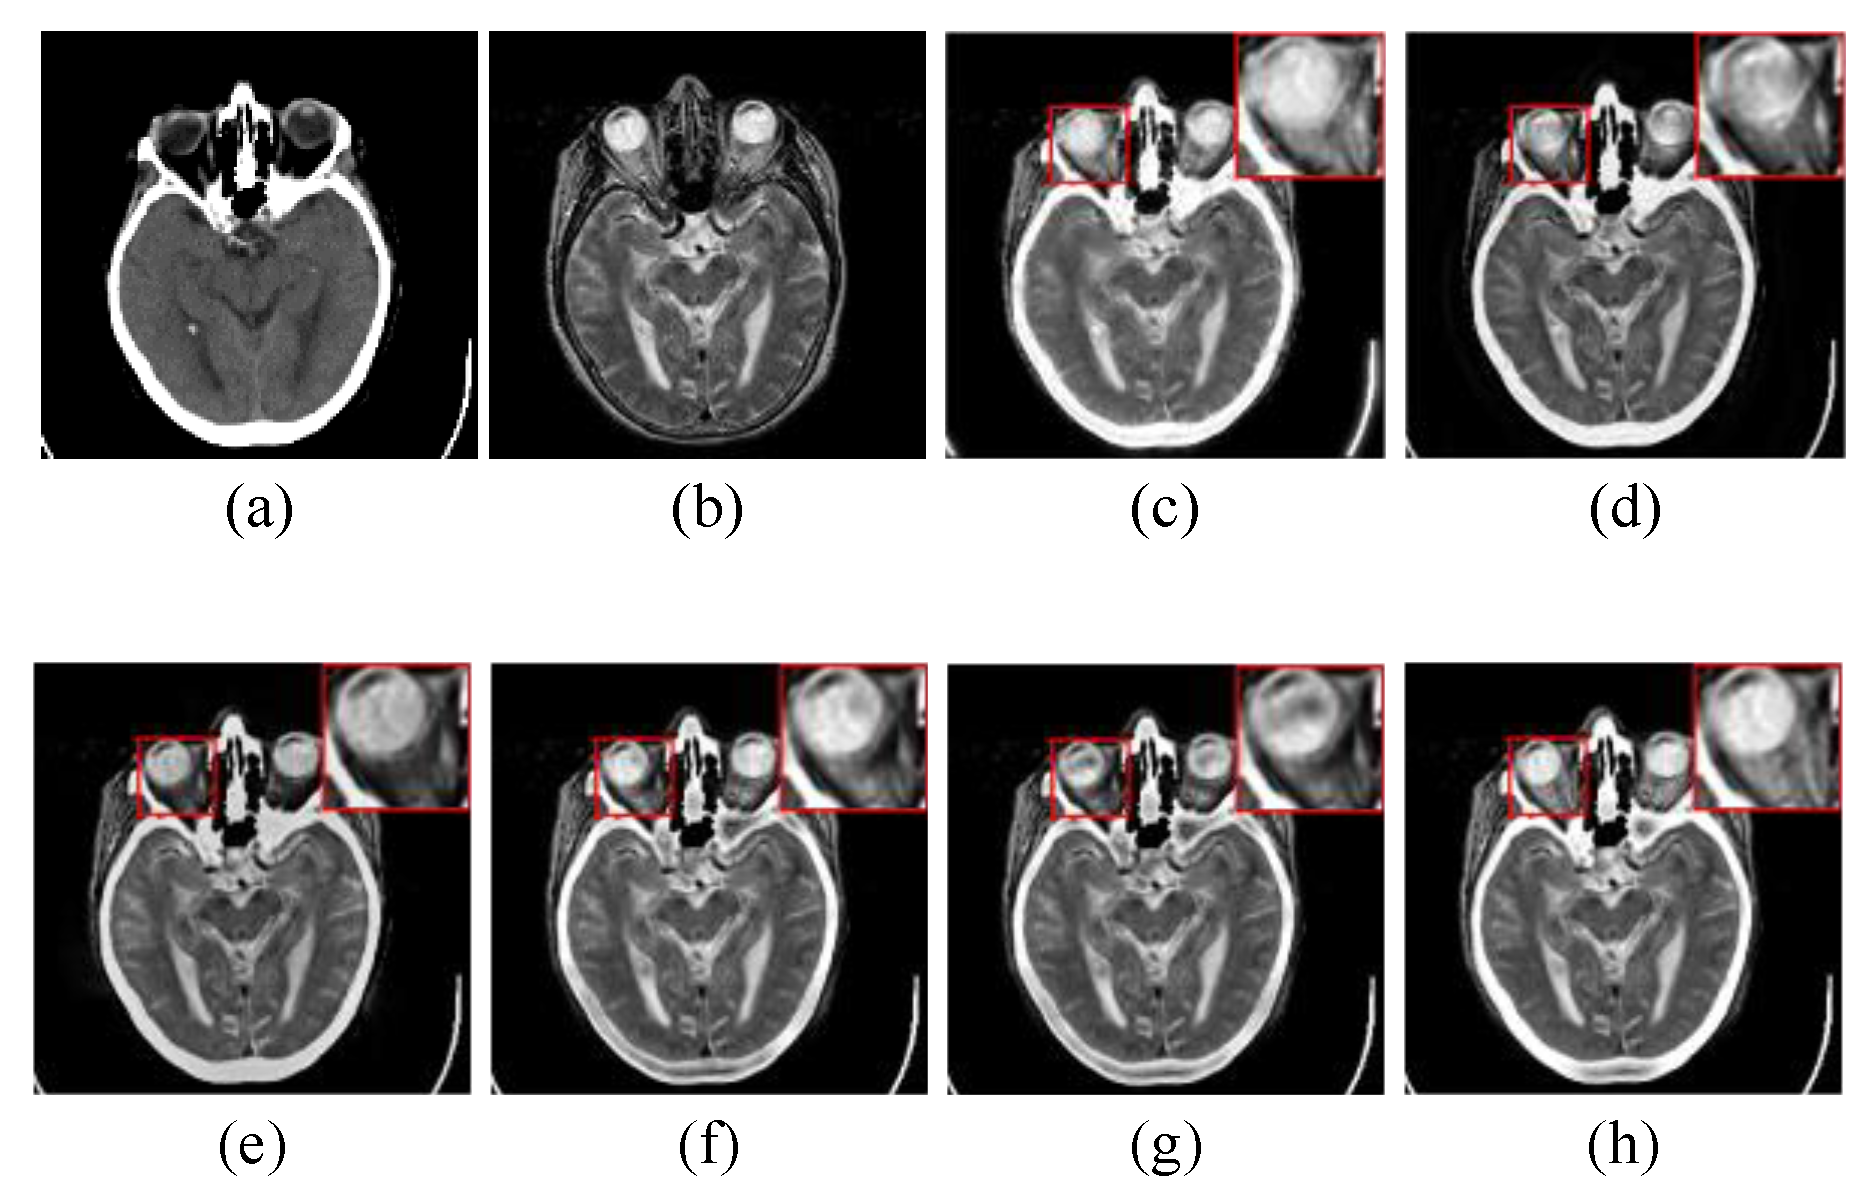

4.2.1. Subjective Visual Evaluation